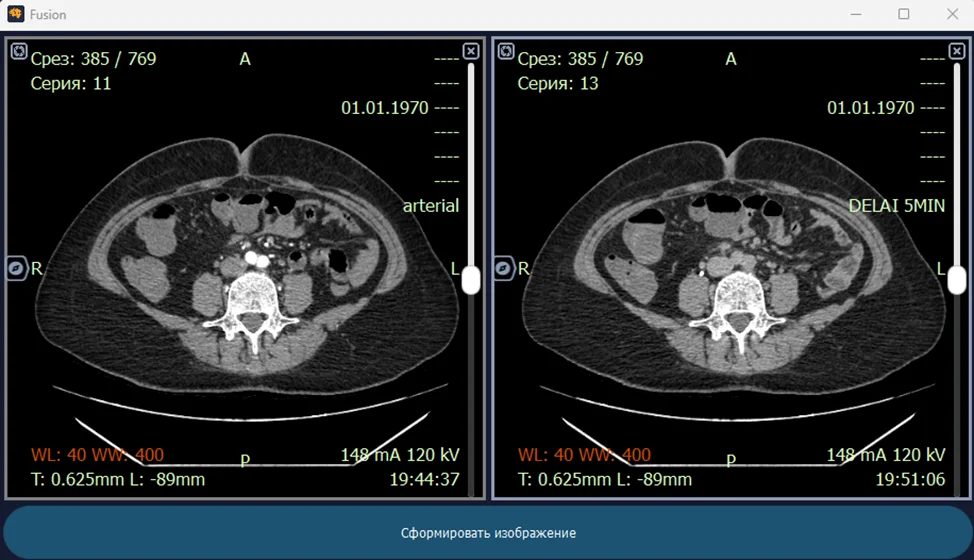

В эпоху цифровой медицины, когда изображения стали неотъемлемой частью диагностики, разработка систем анализа медицинских изображений играет критически важную роль. Мы, как команда разработчиков, погрузились в мир DICOM (Digital Imaging and Communications in Medicine) – международного стандарта для хранения, передачи и визуализации медицинских изображений. Наш опыт показывает, что это не просто задача кодирования, а настоящее искусство интерпретации визуальной информации для помощи врачам в постановке точных диагнозов.

DICOM – это больше, чем просто формат файла. Это целый протокол, определяющий, как медицинские изображения и связанная с ними информация должны быть структурированы, переданы и отображены. Этот стандарт позволяет различным медицинским устройствам и программному обеспечению взаимодействовать друг с другом, обеспечивая беспрепятственный обмен данными между больницами, клиниками и врачами.

- Получение и декодирование DICOM-изображений: Извлечение пиксельных данных и метаданных.

- Предобработка изображений: Удаление шума, коррекция контрастности и другие методы улучшения качества изображения.

- Сегментация: Выделение интересующих областей (например, опухолей) на изображении.

Медицинские изображения, полученные с помощью различных методов визуализации (рентген, КТ, МРТ), зачастую страдают от шума, низкой контрастности и артефактов. Предобработка играет решающую роль в улучшении качества изображений, делая их более пригодными для анализа и интерпретации.

Мы используем различные методы предобработки, в зависимости от типа изображения и конкретной задачи. Некоторые из наиболее распространенных методов включают: